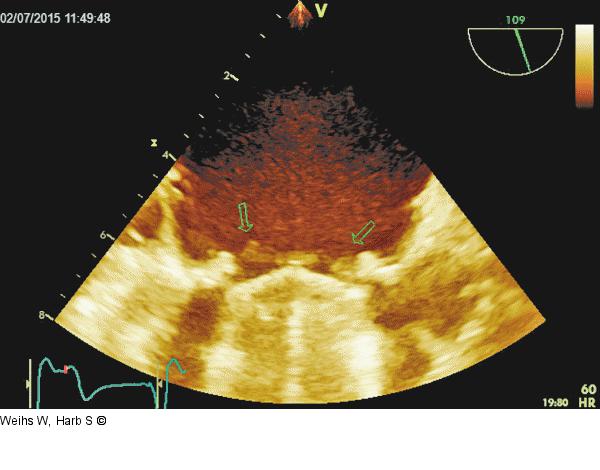

Abbildung 1: Mitralklappenprothese Mehrere teilweise flottierende Vegetationen an der atrialen Seite der Mitralklappenprothese. |

Mehrere teilweise flottierende Vegetationen an der atrialen Seite der Mitralklappenprothese. |